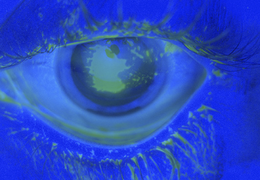

Eye

Acute angle closure glaucoma (right)

Anterior uveitis with hypopyon

Airbag corneal abrasion

External stye

Internal stye